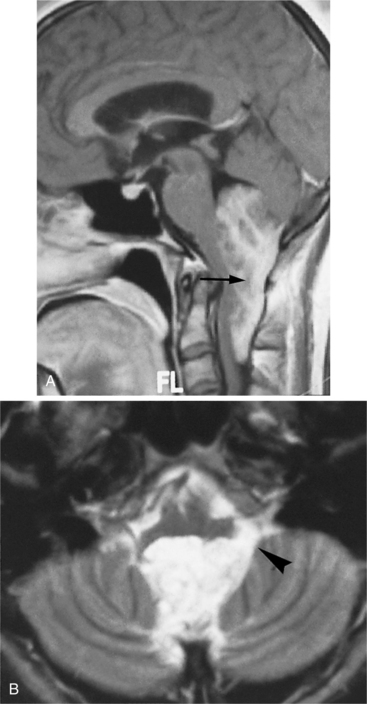

Clinical Manifestations.: Ependymoma is more common in the fourth ventricle and is likely to be detected early because of the signs and symptoms of increased ICP in the posterior fossa (e.g., headache, nausea, vomiting, and papilledema). However, supratentorial ependymomas often grow large before detection. Fig. 30-7 depicts an ependymoma of the fourth ventricle.

Figure 30-7 Ependymoma of the fourth ventricle. Sagittal gadolinium-enhanced T1-weighted (A) and axial T2-weighted (B) magnetic resonance images. A heterogeneously enhanced mass (arrow) fills the lower half of the fourth ventricle and extends through the foramina of Luschka (arrowhead) and Magendie to lie posterior to the medulla oblongata and upper cervical spinal cord, which are compressed from behind. There is obstructive hydrocephalus. (From Grainger and Allison’s diagnostic radiology: a textbook of medical imaging, ed 4, Philadelphia, 2001, Churchill Livingstone.)